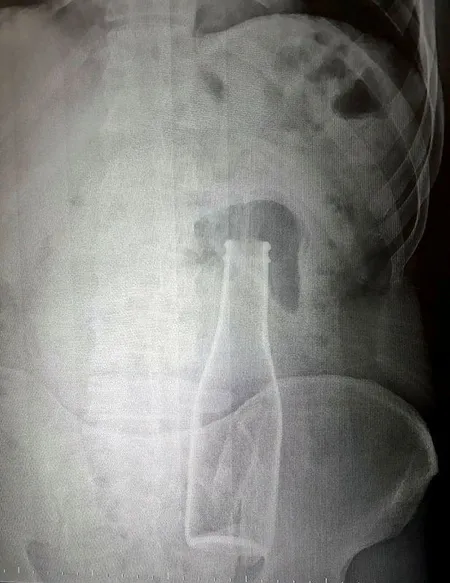

Karaman Eğitim ve Araştırma Hastanesi'ne, 28 Haziran Pazar gecesi gelen A.E., karın ağrısı şikayeti olduğunu söyledi. Bunun üzerine röntgen filmi çekilen gencin kalın bağırsağında şişe olduğu görüldü. Makattan girdiği belirlenen şişe, yaklaşık 1 saat süren ameliyatla çıkarıldı.